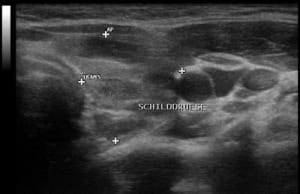

U.a. weisen Gewichtsveränderungen, Zyklusunregelmäßigkeiten und emotionale Instabilität auf Schilddrüsenfunktionsstörungen hin. Derbe Veränderungen in der Schilddrüse hingegen sind verdächtiger als weiche. Zu jeder Schilddrüsenuntersuchung gehört auch der Ultraschall von Schilddrüse und Halsweichteilen (Schilddrüsensonographie). Hierdurch lassen sich Größe und evtl. Veränderungen erkennen sowie relevante Strukturen in der vorderen Halsregion mit beurteilen, insbesondere Nebenschilddrüsen und Lymphknoten. Anhand des Schallmusters und des Durchblutungsmusters (Perfusion) lassen sich häufig bereits Krankheitsbilder festmachen.

So findet sich bei einer Autoimmunhyperthyreose (M. Basedow), einer zumeist schweren Form einer Schilddrüsenüberfunktion, eine ausgeprägte Echoarmut in Verbindung mit einer stark vermehrten Durchblutung des Schilddrüsengewebes. Von den Knoten verdienen solche mit Mikroverkalkungen und einer vermehrten Binnenperfusion verstärkte Aufmerksamkeit.